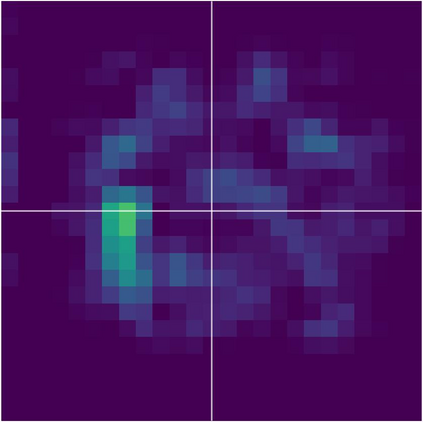

Various imaging modalities allow for time-dependent image reconstructions from measurements where its acquisition also has a time-dependent nature. Magnetic particle imaging (MPI) falls into this class of imaging modalities and it thus also provides a dynamic inverse problem. Without proper consideration of the dynamic behavior, motion artifacts in the reconstruction become an issue. More sophisticated methods need to be developed and applied to the reconstruction of the time-dependent sequences of images. In this context, we investigate the incorporation of motion priors in terms of certain flow-parameter-dependent PDEs in the reconstruction process of time-dependent 3D images in magnetic particle imaging. The present work comprises the method development for a general 3D+time setting for time-dependent linear forward operators, analytical investigation of necessary properties in the MPI forward operator, modeling aspects in dynamic MPI, and extensive numerical experiments on 3D+time imaging including simulated data as well as measurements from a rotation phantom and in-vivo data from a mouse.